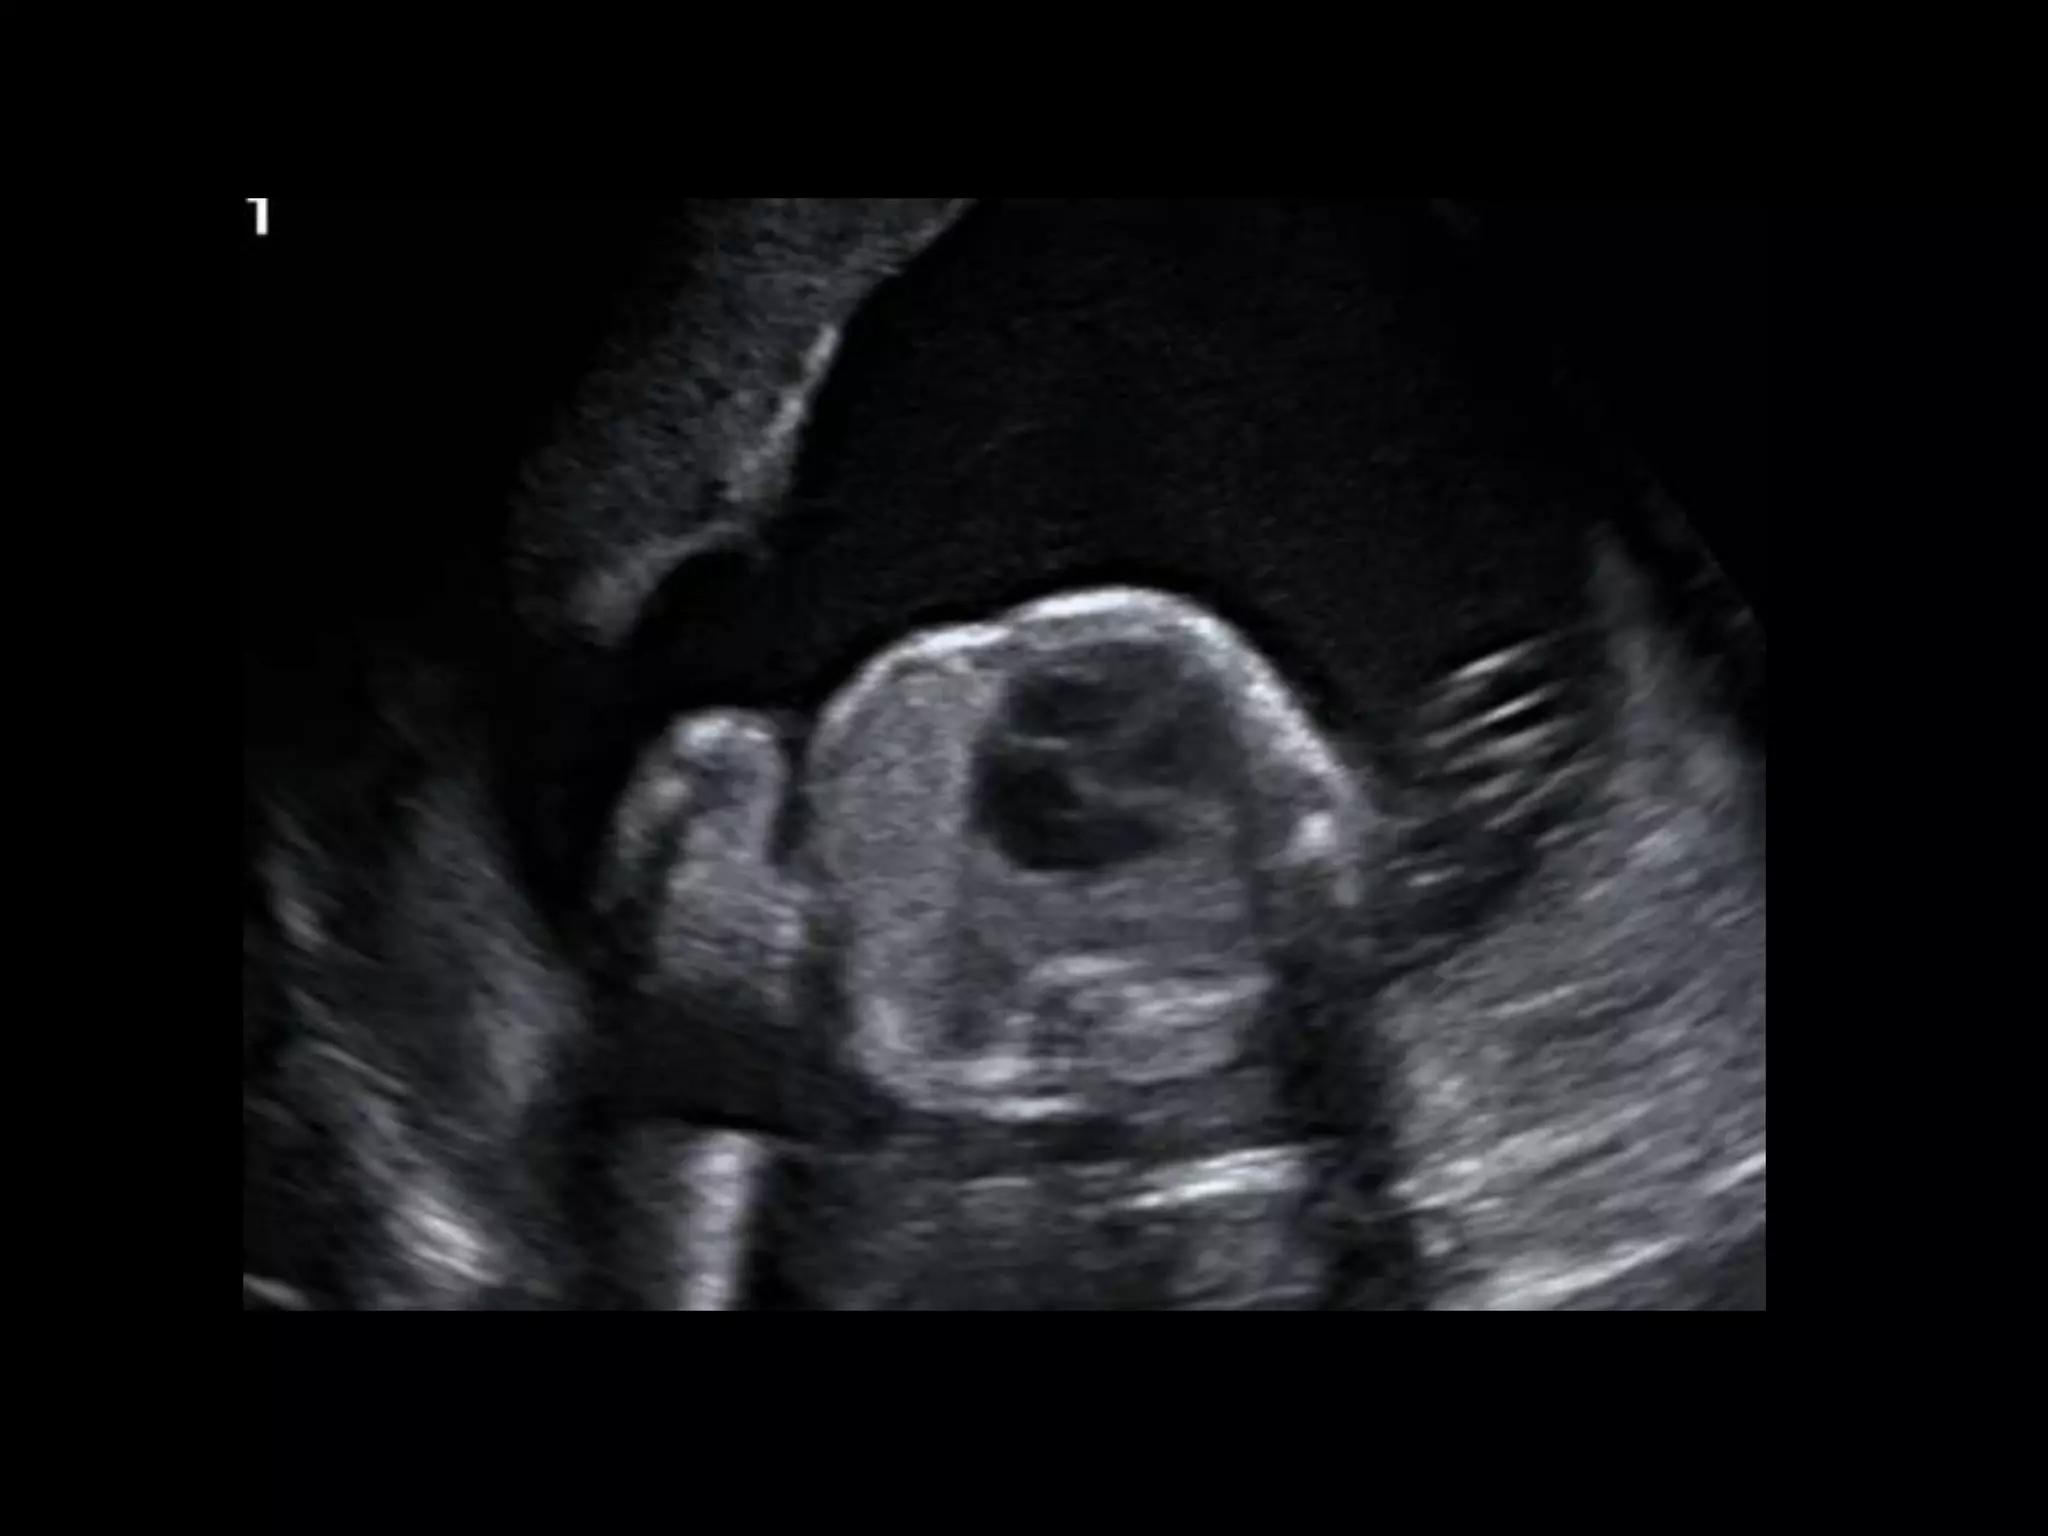

โ€ข 36 yo female 30.5 weeks pregnant

โ€ข Referred with โ€žmultiple fetal anomaliesโ€Ÿ for

fetal ultrasound

-Cephalic

-Heart - right side

-Stomach โ€“ right side

-Liver โ€“ left side

-Des colon โ€“ right side

Situs Inversus Totalis

โ€ข 3-5% with cardiac abnormalities

โ€ข 25% with primary ciliary dyskinesia (PCD)

โ€“ Kartagenerโ€Ÿs Syndrome

โ€“ Chronic sinus infections; respiratory infections;

infertility